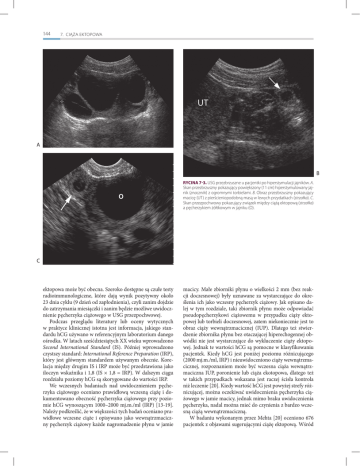

RYCINA 7-3. USG przezbrzuszne u pacjentki po hiperstymulacji jajników. A.

Skan przezbrzuszny pokazujący powiększony (11 cm) hiperstymulowany jajnik (znaczniki) z ogromnymi torbielami. B. Obraz przezbrzuszny pokazujący